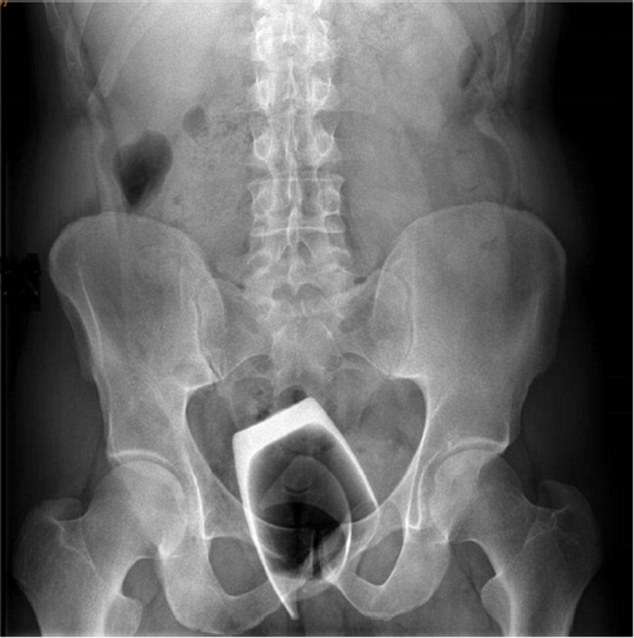

Upon physical examination, there was no evidence of abdominal guarding or bleeding from the man’s rectum. Abdominal and pelvic X-rays were performed to verify the presence of a broken glass, which was approximately 3 inches by 2 inches in size.

An X-ray showed the glass in his rectum, its bottom-side facing up.